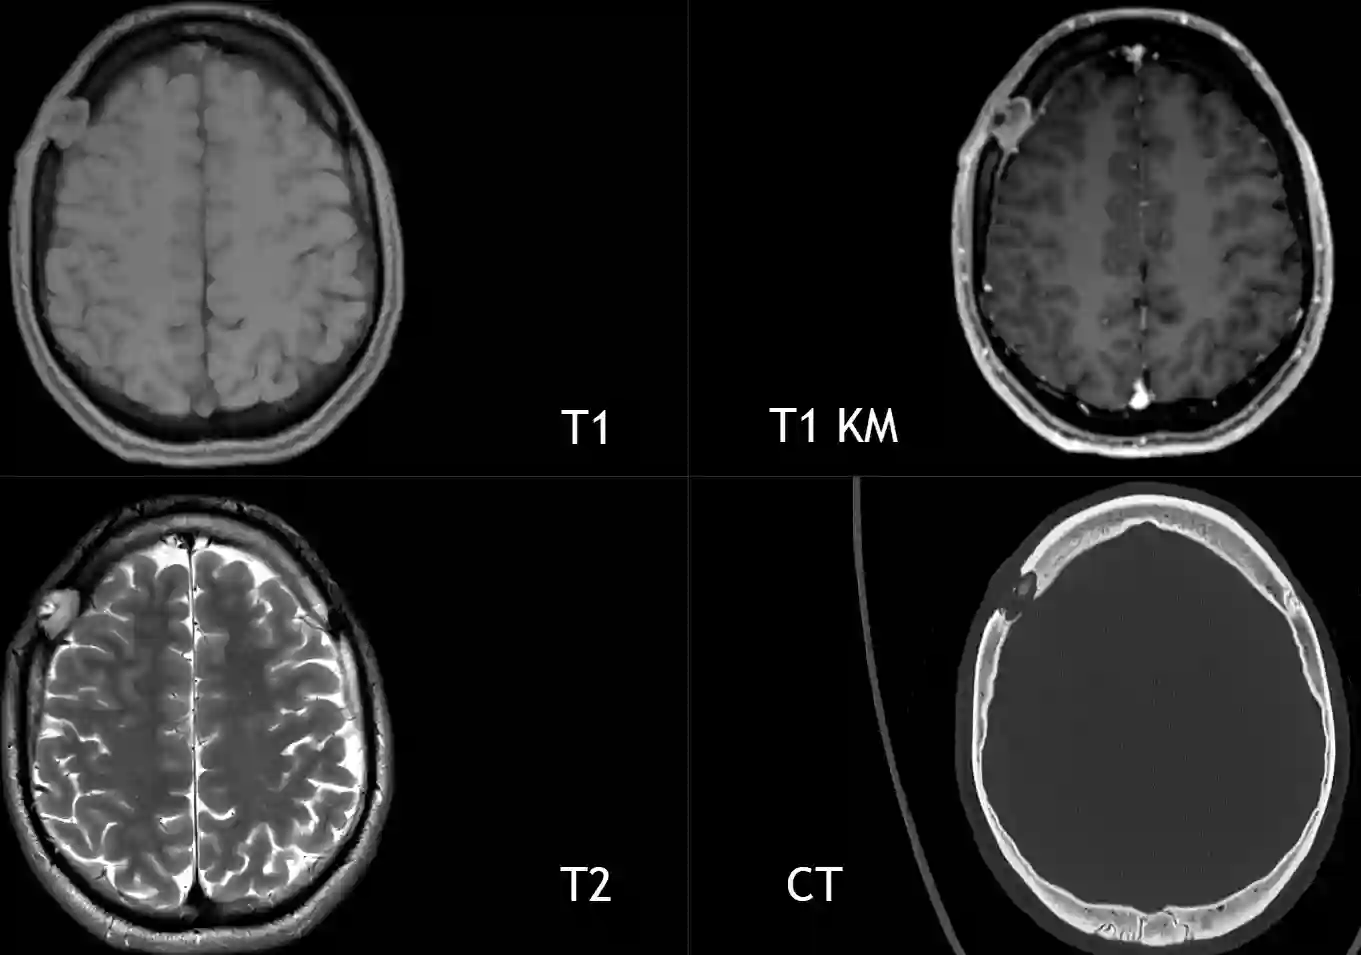

CT und MRI einer intrakraniellen Langerhans-Zell-Histiozytose

MRI und CT Bild eines Patienten mit einer histopathologisch gesicherten intrakraniellen Langerhans-Zell-Histiozytose.